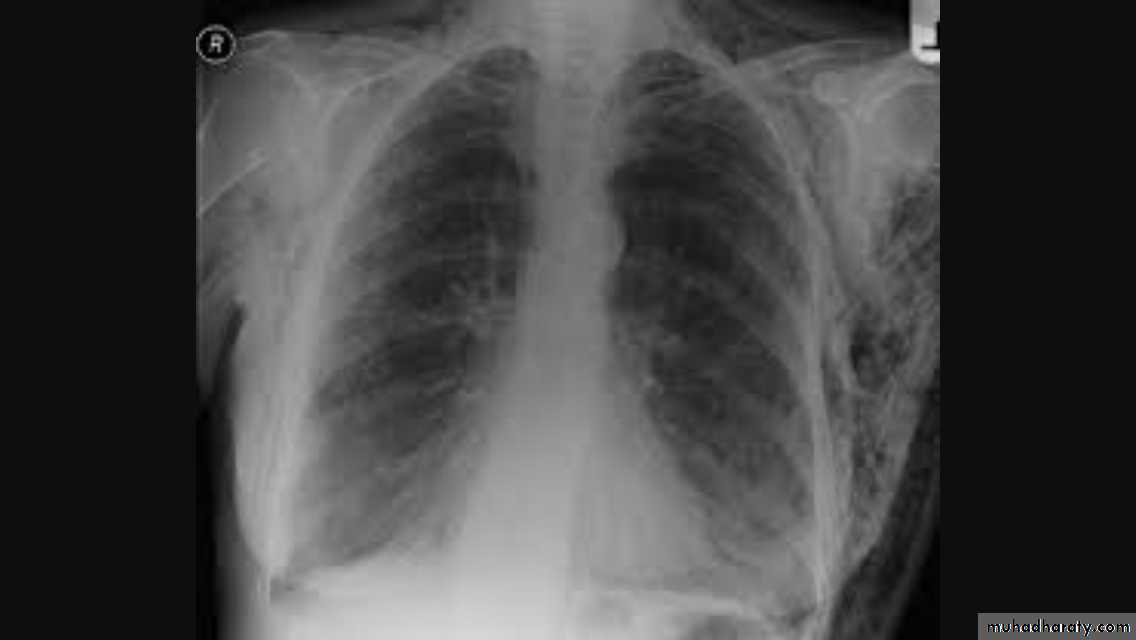

Hila

Left hilum is higher than theRt in 97%

Both hila should be equal density & size with concave lateral borders

Upper limbs of hila ( superior pulmonary veins)Lower limbs of hila ( inferior

pulmonary arteries )

Normal LNs not visible at CXR